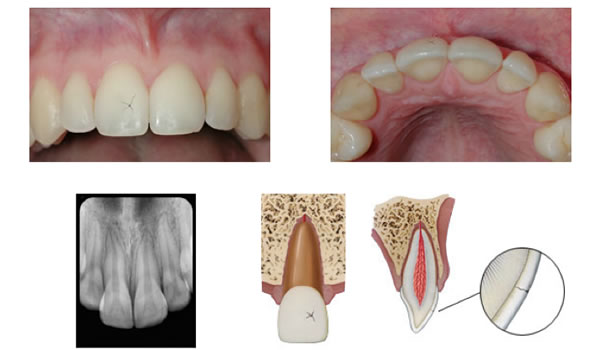

Crown infraction

Figure 1. Crown infractions are only evident in a clinical setting. Radiographs will typically not reveal small cracks in the enamel.

An infraction is shallow crack that is entirely contained within the enamel and does not continue into the dentin (Figure 1). There is no loss of tooth structure and very little risk of pulpal inflammation or necrosis. Infractions will unavoidably happen to every single tooth in your mouth given enough time, as they are a natural result of normal wear and tear. I work under a surgical operating microscope on every case and I see infractions all day long. Sometimes they are visible even to the naked eye. Provided vitality testing is WNL, there is no treatment recommended unless the patient expresses an esthetic concern, in which case veneers or crowns may provide a solution.